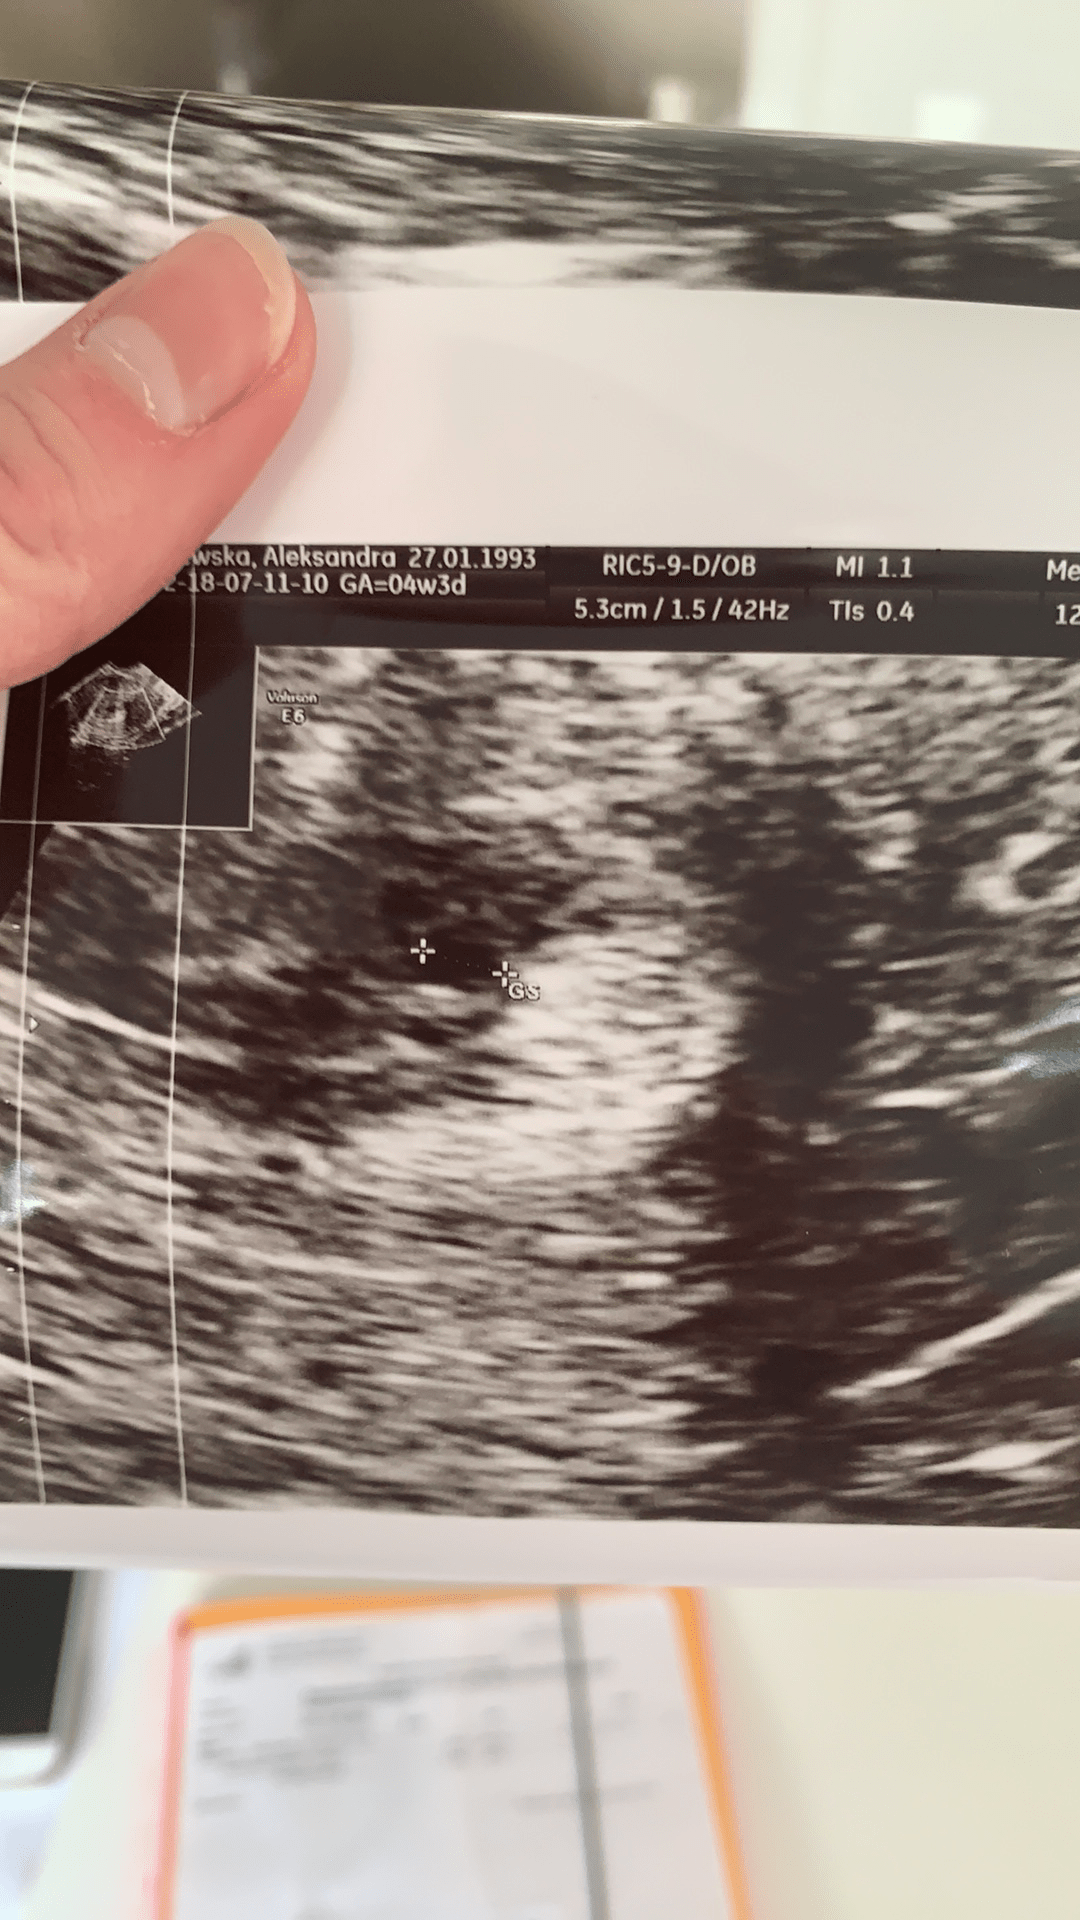

kochana a to nie jest ciałko żółte? Nie mówił co to? 🧡

on jakoś powiedział że ciałko żółte jest obok płodziku. Tak to ujął, ale ja nie skumałam, a nie wiem czemu głupio mi było dopytać. Tak mnie to sparaliżowało, że ciąża jednak jest w macicy że nie dopytałam. Po pozamacicznej mam taki lęk, że cały czas nogi mi drżały podczas USG.

Szok pęcherzyk ciążowy przy becie około 400-450 😍

• 2D78B684-D18C-48B8-8D02-D4AEBBDFFD72.png

2D78B684-D18C-48B8-8D02-D4AEBBDFFD72.png

874,9 KB · Wyświetleń: 157